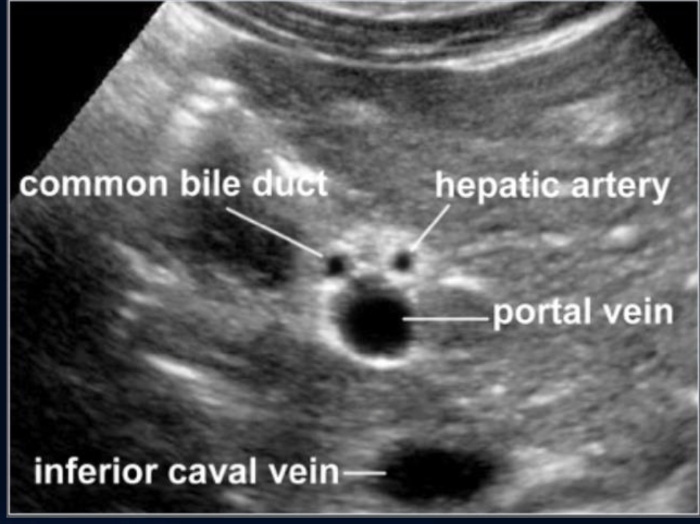

Label Anatomy of PortaHepatis TRV